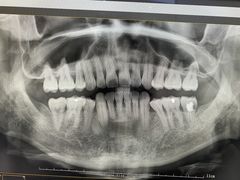

报错

• -牙博士口腔品牌连锁(杨浦店)

点小评5596777448 | 22-02-22